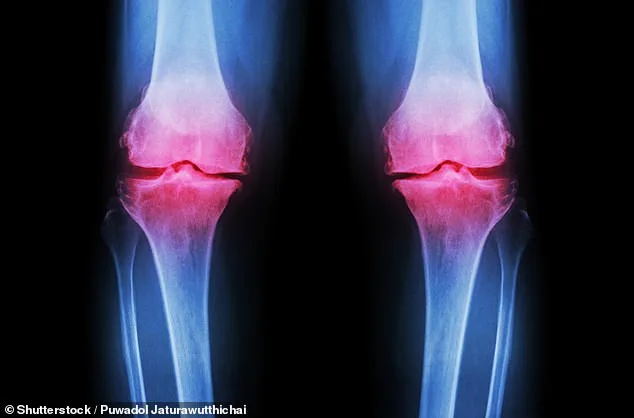

Experts caution that the study's short duration limits its long-term implications. Bone thinning is a slow process, often only detected through a Dexa scan—a test that measures bone mineral density. Scores below -2.5 indicate osteoporosis, but the study's participants were not assessed using this metric. Nonetheless, the results align with existing evidence that protein-rich diets, when paired with exercise, can bolster bone health. Public health advisories already emphasize the importance of protein, vitamin D, and weight-bearing activities, but this research adds a new layer of clarity.